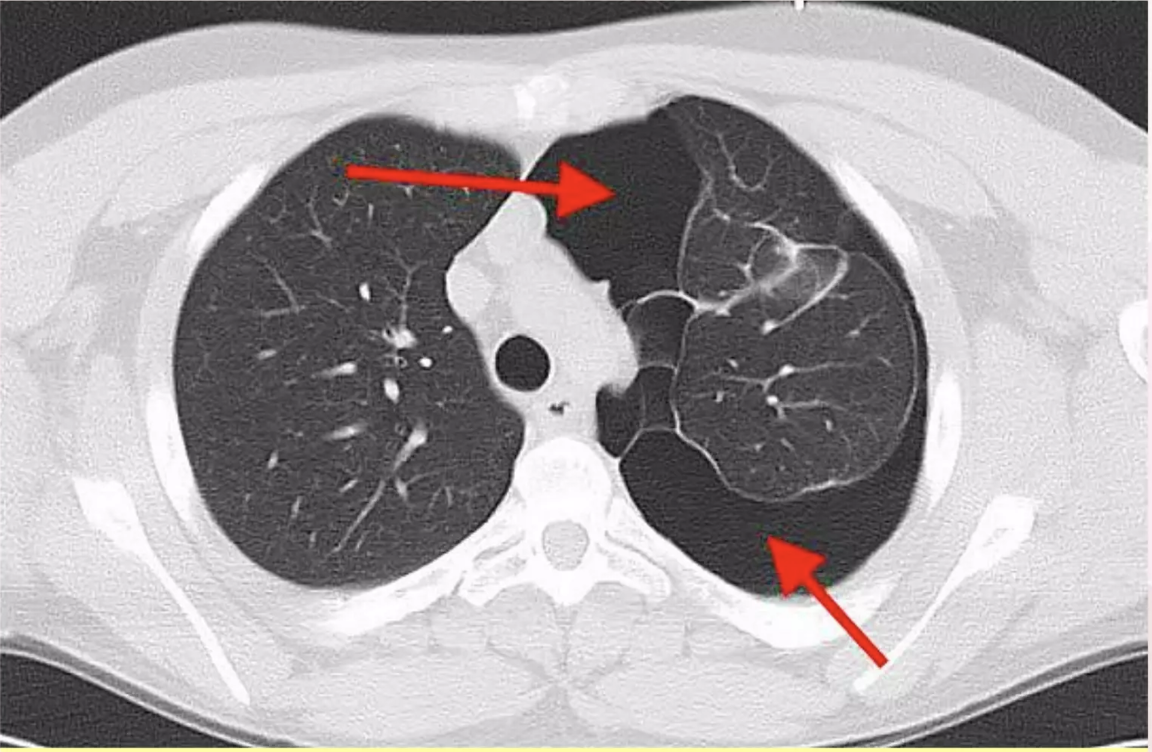

?

A

Acute respiratory distress syndrome

- normal heart

-no pleural effusion

-bilateral widespread pulmoonary inflitrates

-air bronchograms

11

Q

12